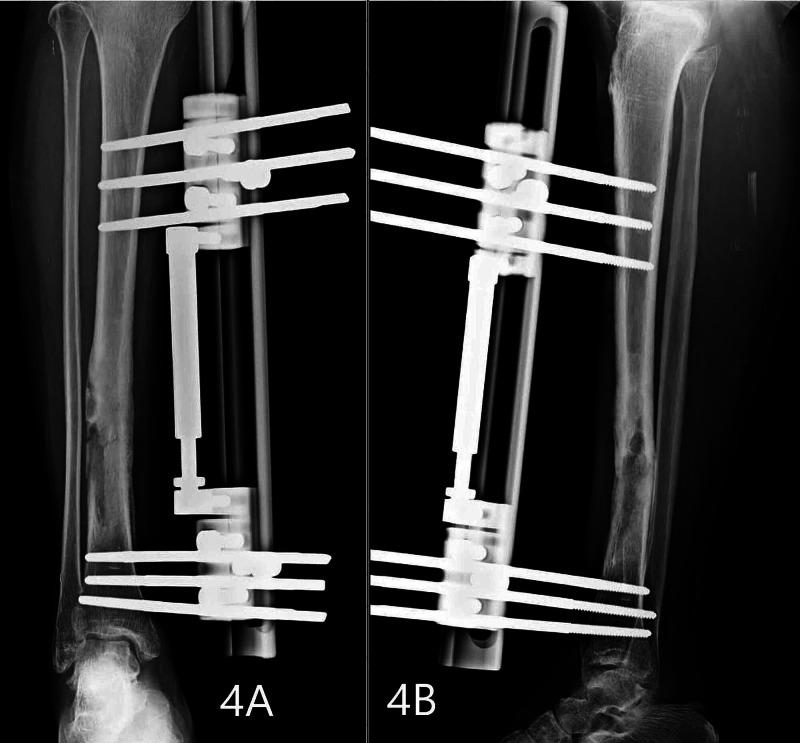

Salmonella osteomyelitis is usually seen in patients with hemoglobinopathies and immunodeficient individuals. However, it is a rare clinical entity in an immunocompetent person with very few cases reported in clinical literature usually caused by non-typhoid Salmonella. Here, we report a case of osteomyelitis of the right tibia in a 40-year-old immunocompetent lady. She developed a pathological fracture of the right tibia during the course of her treatment. It was then managed successfully by debridement and external fixation using a rail fixator. Salmonella osteomyelitis does not present with unique clinical or radiological signs. High index of suspicion with appropriate testing will help in determining the causative agent correctly and thus aid in its successful management.

沙门氏菌骨髓炎通常见于患有血红蛋白病的患者和免疫功能低下的个体。然而,在免疫功能正常的人中,这是一种罕见的临床病症,临床文献中报道的病例很少,通常由非伤寒沙门氏菌引起。在此,我们报告一例40岁免疫功能正常女性的右胫骨骨髓炎病例。她在治疗过程中发生了右胫骨病理性骨折。随后通过清创术和使用轨道固定器进行外固定成功治疗。沙门氏菌骨髓炎没有独特的临床或放射学征象。高度怀疑并进行适当检测将有助于正确确定病原体,从而有助于其成功治疗。